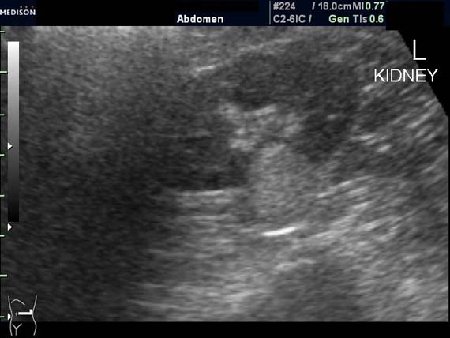

Женщина 50 лет. Жалоб нет. Обследование перед поездкой в санаторий по поводу дисфункции гепатобилиарной системы.

Случайная находка в нижней трети левой почки (не в полюсе, а по задне-медиальной поверхности).

Образование в левой почке

При ультрасонографии ангиомиолипома выглядит как округлое образование без капсулы с однородной внутренней эхоструктурой и четкими контурами; эхогенность ее чаще всего равна или чуть выше эхогенности перинефральной клетчатки [7]. Значительно реже эхогенность ангиомиолипом может быть равна эхогенности почечной паренхимы; такие опухоли состоят почти полностью из гладкомышечной ткани [8]. Иногда позади ангиомиолипомы может определяться слабая акустическая тень.